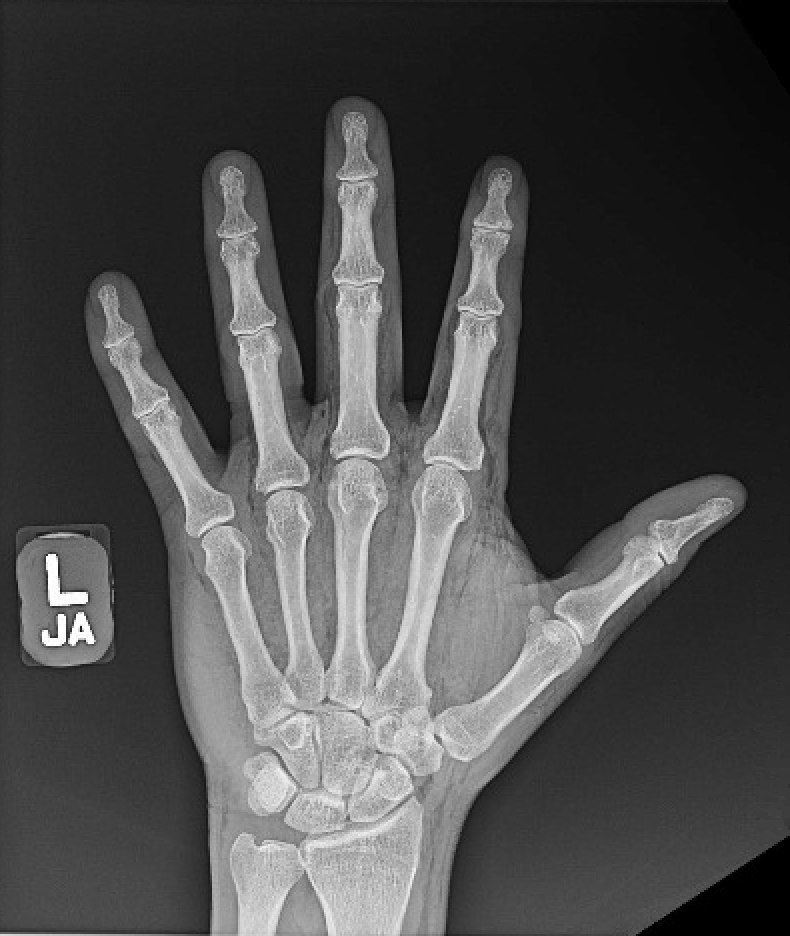

High Pressure Hand Injection Injury. AP Xray, Annotated. JETem 2020 JETem High-Pressure Injection Injury Symptoms High pressure injection injuries are uncommon injuries that require immediate attention. Symptoms and signs of hpi injuries. Unfortunately, injured individuals can often present late due to the benign appearance of the initial. In an hpi injury, the puncture wound is small and not distinct; Pain and local swelling is minimal until. The pain and swelling around the. An hpi injury. High-Pressure Injection Injury Symptoms.